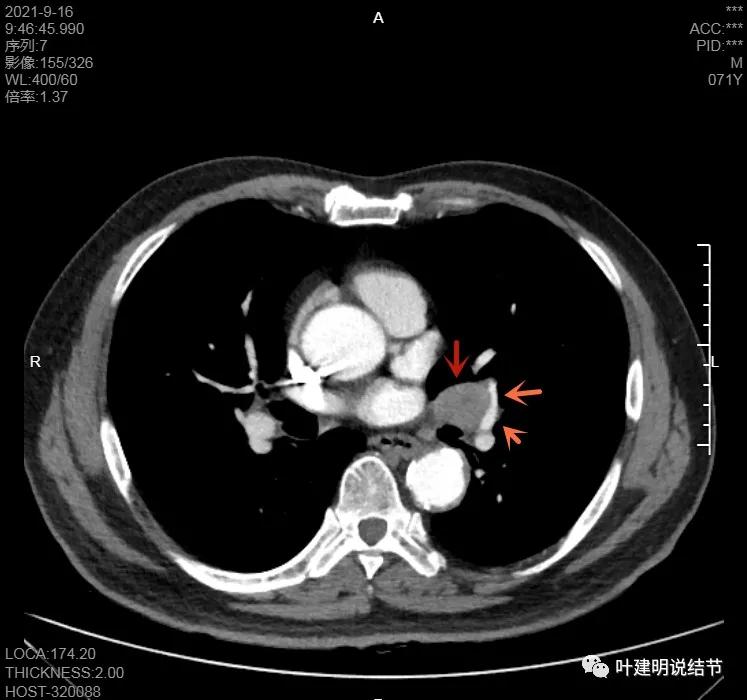

左下病灶在增强CT中强化不明显,但有肺门区肿大淋巴结,而且近3厘米大。同事叫我看片子的时候,本来只先看左下病灶处,以为是良性结节。但翻到肺门区,发现有如此大的肿大淋巴结,那这个原发灶则肯定是恶性的了!我们先来看纵隔窗的淋巴结情况:

左肺门区淋巴结肿大

肺门区淋巴结挤压附近肺血管,但似乎示见肿瘤侵犯破坏血管壁